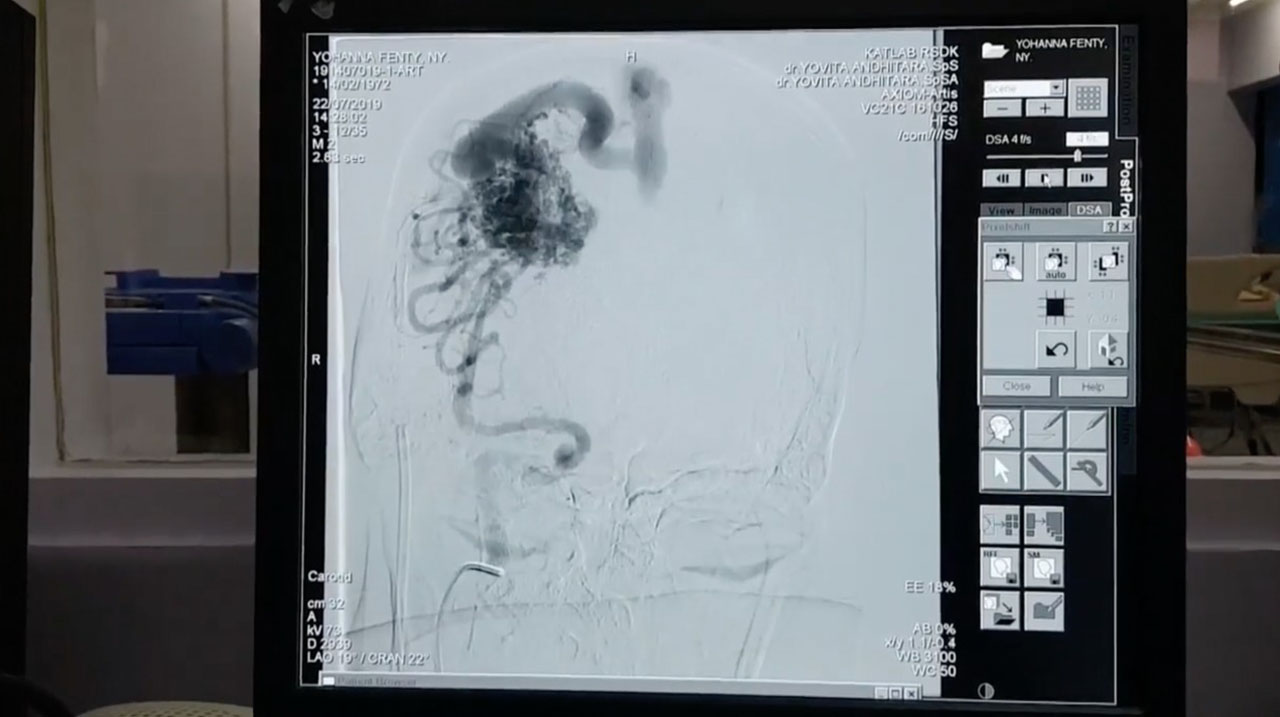

CATHETERIZATION LABORATORY (CATH LAB)